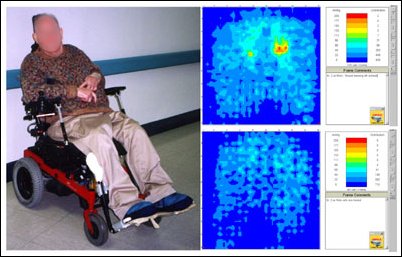

Technologia mająca na celu stworzenie Mapy Ucisku na skórę jest to narzędzie wykorzystujące komputer, niezbędne oprogramowanie, elastyczną podkładkę z czujnikami, jednostkę elektroniczną i źródło energii (Zdjęcie 1). Doktor Betz używa podkładkę z czujnikami wyprodukowaną przez Roho Group, Inc. Mierzy ona około 46 x 46 centymetrów i zawiera 1296 czujników, które odbierają impulsy kiedy wywierany jest na nie ucisk.

Zdjęcie 1: Oprzyrządowanie Mapy Ucisku: komputer z oprogramowaniem, podkładka z czujnikami oraz jednostka elektroniczna.

Podkładkę z czujnikami umieszcza się pomiędzy siedziskiem a pośladkami osoby siedzącej, informacje o wywieranym ucisku na skórę są wyświetlane na monitorze. Kolory i numery na monitorze odpowiadają poziomowi ucisku wywieranego na skórę pacjenta wyrażane w milimetrach słupka rtęci (mmHg). Każdy z czujników pokazuje swój odczyt ciśnienia, a więc odczyt całości to obraz 1296 oddzielnych wyników. (Patrz zdjęcie 2.)

Rysunek 2: Mapa Ucisku pokazuje obszary o małym i dużym ucisku podczas siedzenia. Kolory i numery na ekranie odzwierciedlają poziom ucisku wyrażany w milimetrach słupka rtęci. (mmHg).

Zdjęcie 2 pokazuje dwie Mapy Ucisku tej samej osoby siedzącej na dwóch różnych poduszkach. Poduszka z prawej strony ukazuje nam korzystniejszą Mapę Ucisku dla pacjenta i prawdopodobnie byłaby lepszym wyborem do codziennego stosowania.